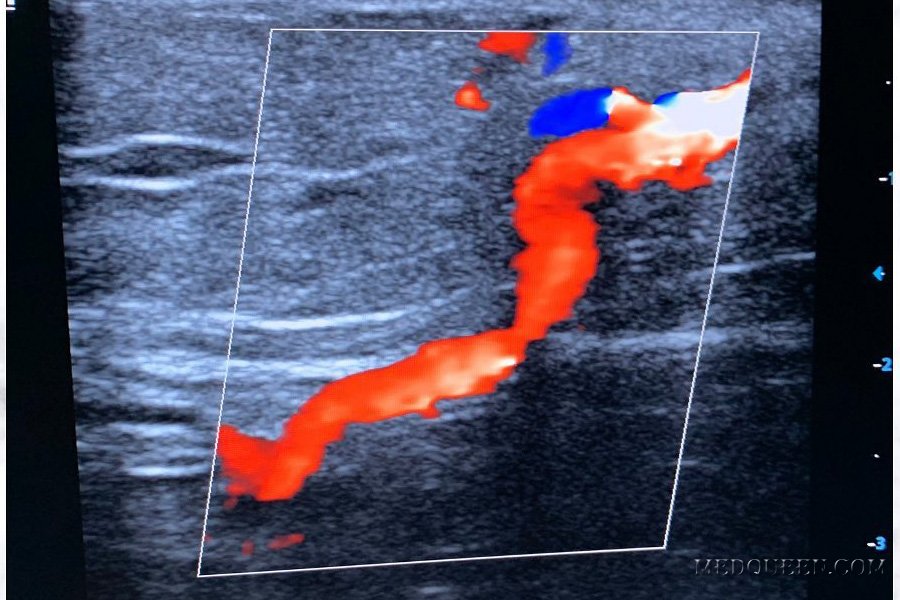

Исследование артерий матки: хорошее изображение волны при допплерографии маточной артерии можно получить, если сперва идентифицировать внутреннюю подвздошную артерию матери. После этого датчик немного перемещают в краниальном направлении и медиально до тех пор, пока не будет визуализироваться цветное обзорное изображение маточных сосудов в миометрии. Затем для получения изображения волны датчик располагают над артерией. Волну легко распознать по форме и меньшей частоте, которая совпадает с пульсом матери (рисунок 1).

Рисунок 1. Допплерография маточной артерии. А – волна нормального кровотока в маточной артерии в I триместре беременности. B– волна нормального кровотока в маточной артерии в начале II триместра беременности (до 18 недели). C– волна нормального кровотока в маточной артерии в III триместре. D– волна аномального кровотока в маточной артерии на 24 неделе беременности: отмечается недостаточный диастолический кровоток и углубление (протодиастолическая выемка), демонстрирующее высокое сопротивление кровотоку

Цветное изображение используют для визуализации кровотока в главной маточной артерии, которая находится медиальнее наружной подвздошной артерии (датчик нужно разместить на участке максимального цветового насыщения). Цветное изображение кровотока позволяет получить необходимые надежные данные, а также сократить время наблюдения, снизить интра- и интеробсервационные коэффициенты вариабельности.